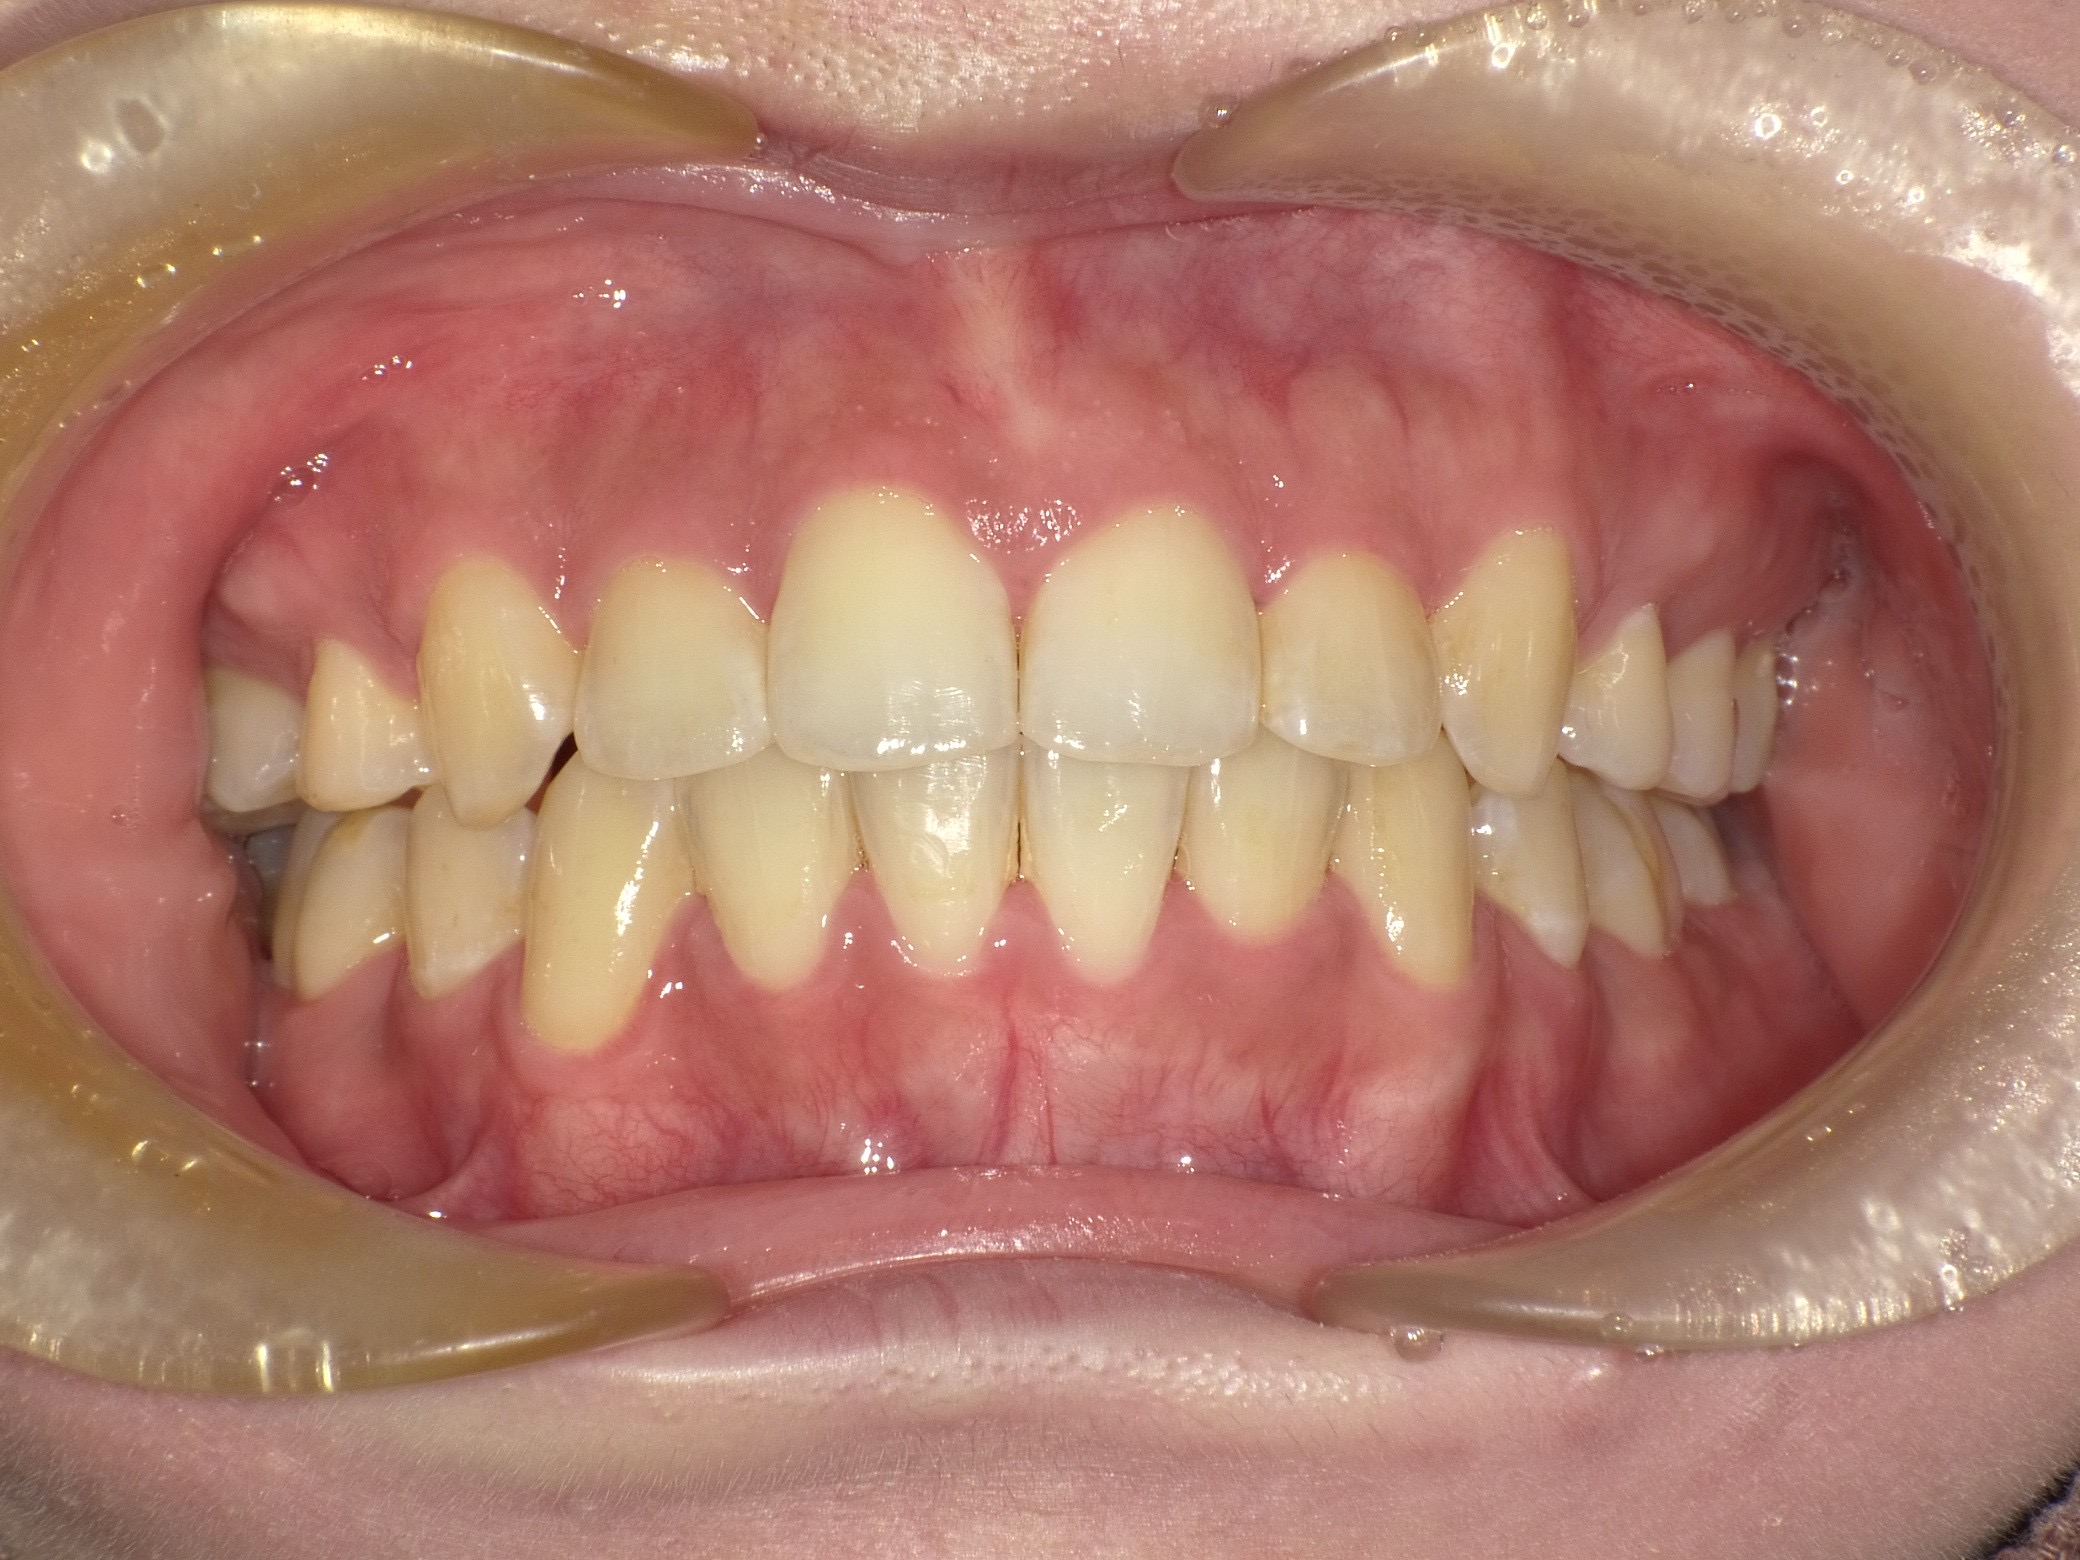

症例④

症例4_治療前 症例4_治療後

年齢・性別 24才男性

治療方法 ホワイトブラケット

治療期間 3年

治療総額 850,000円

特記事項 抜歯あり

リスク・副作用 治療の初期段階では痛みや不快感が生じやすくなりますが、1週間前後で慣れます